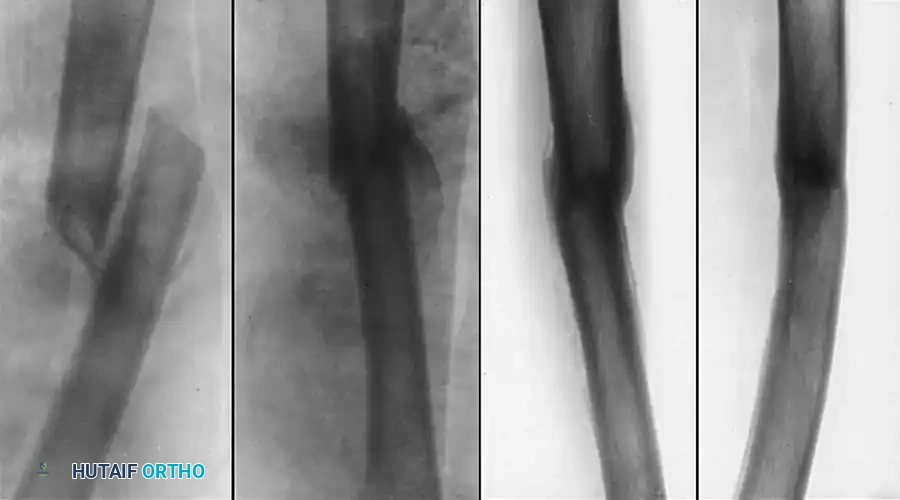

When significant shortening accompanies the malunion, one-stage femoral lengthening can be performed, though it is technically demanding. Kempf, Grosse, and Abalo popularized the Z-step osteotomy stabilized with a dynamically locked intramedullary nail.

Fig. 55-21 One-stage femoral lengthening: reaming, Z-shaped osteotomy, lengthening, static locked medullary nailing, transverse screws, and bone grafts.

Surgical Warning: Acute lengthening of the femur beyond 3-4 cm carries a high risk of femoral or sciatic nerve neurapraxia. Kempf et al. recommended keeping the patient on strict bed rest with the hip flexed 30 degrees and the knee flexed 90 degrees for 48 hours postoperatively to relax the neurovascular tension.

Murray, Kambouroglou, and Kenwright reported excellent results with one-stage lengthening (averaging 4 cm) using diaphyseal osteotomies stabilized by IM nails or plates, provided the soft tissue envelope was pristine. They emphasized that extensive scarring or previous infection are absolute contraindications for acute one-stage lengthening, favoring gradual distraction osteogenesis in such scenarios.

Complex multi-planar correction utilizing advanced osteosynthesis techniques to restore length and rotation simultaneously.